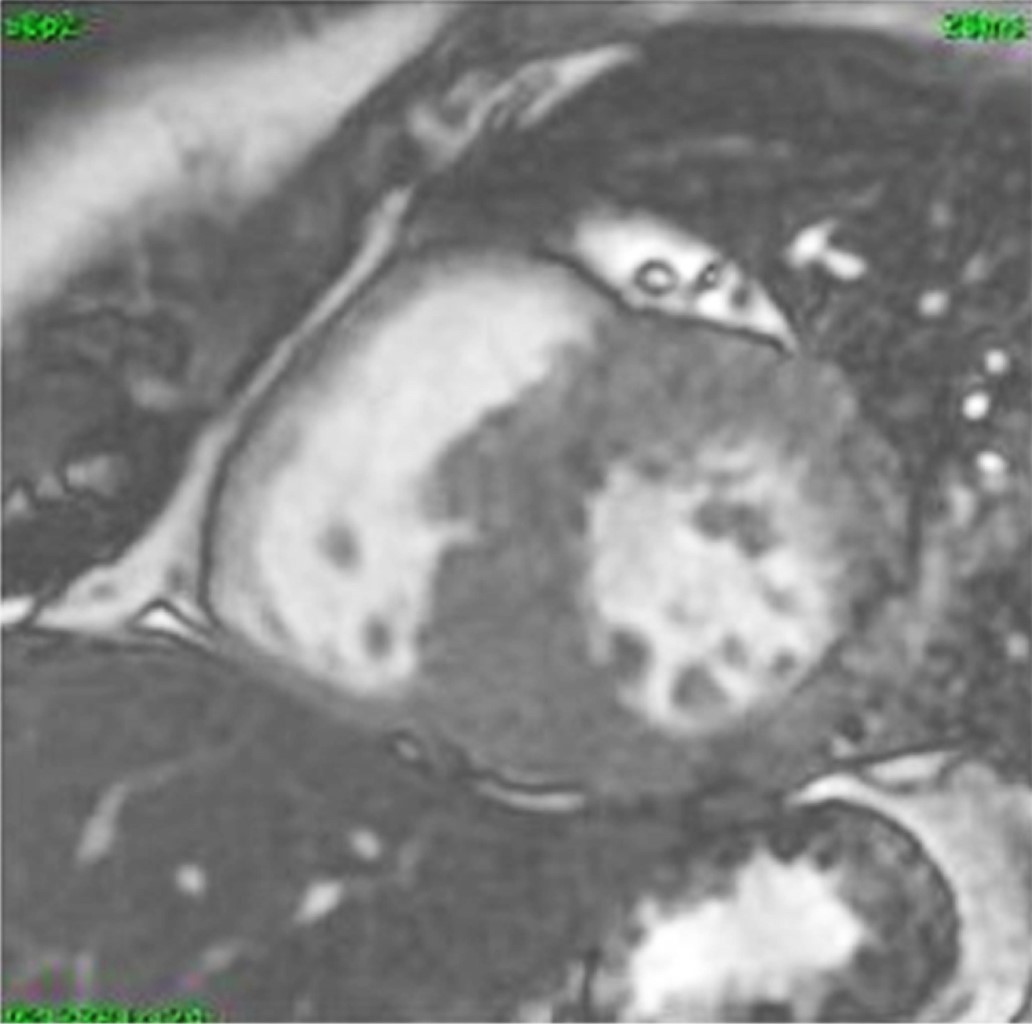

Caso clínico 2: hombre de 30 años, originario de Ciudad de México. Sin antecedentes hereditarios de importancia. Con hipertensión arterial sistémica de 10 años de diagnóstico, tratado con nifedipina 30 mg cada 24 horas; en adecuado control. Diagnóstico de insuficiencia cardiaca congestiva en tratamiento con sacubitrilo/valsartán 50 mg cada 24 horas y carvedilol 12.5 mg cada 24 horas. Hallazgos en resonancia magnética cardiovascular: ventrículo izquierdo ligeramente dilatado con septum de 11 mm, pared posterior del ventrículo izquierdo de 7 mm, diámetro diastólico del ventrículo izquierdo de 55 mm, Diámetro sistólico del ventrículo izquierdo de 45 mm con índice de volumen tele diastólico de 108 mL/m2 e índice de volumen telesistólico de 56.4 mL/m2, masa miocárdica de 143 g con fracción de acortamiento de 18% y fracción de eyección de 48%. Evidencia de hipocinesia septal e inferior a nivel basal y en la pared septal apical. Diagnóstico de cardiopatía dilatada (Figura 2).

Figura 2